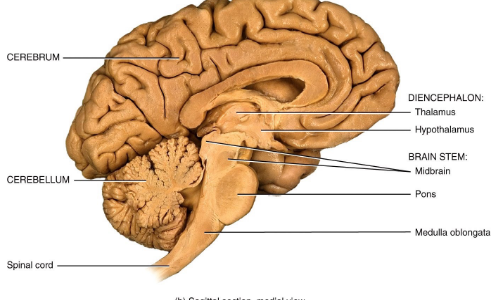

Name four major brain regions.

Cerebrum, Diencephalon, Brainstem, and Cerebellum.

Name the four major regions in the brain (recap).

Cerebrum, Diencephalon, Brainstem, Cerebellum.